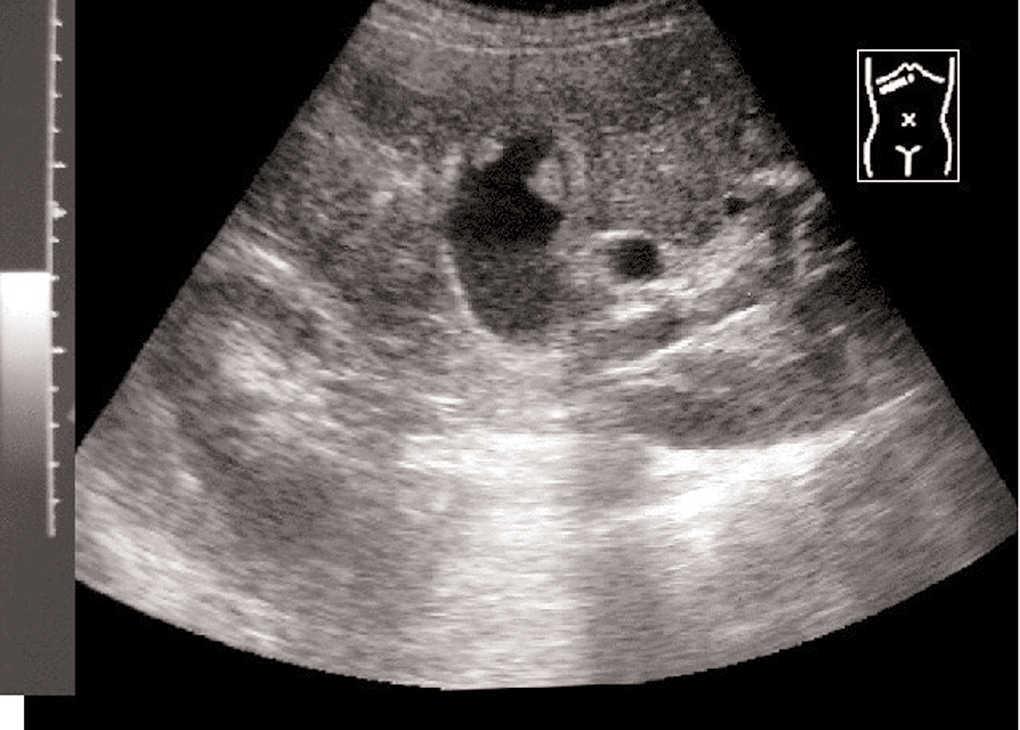

A 47-year-old man presented in July 2000 with progressive jaundice for 3-4 weeks, weakness, and anorexia leading to weight loss, as well as occasional right upper quadrant abdominal pain. He had been under treatment for a depressive syndrome for the previous 5 months and his medication had been changed due to a rise in serum aminotransferases. Liver function tests at admission showed pronounced cholestasis (total bilirubin 13.9 mg/dl, conjugated bilirubin 9.1 mg/dl, alkaline phosphatase 703 U/L, gamma glutamyl transferase 72 U/L) and mild hepatic cell necrosis (alanine aminotransferase 99 U/L (normal < 41 U/L) aspartate aminotransferase 44 U/L (normal < 37 U/L) without liver failure. Ultrasound showed intra- and extrahepatic bile duct dilation with several nodules on the gallbladder wall (fig. 1). Magnetic resonance cholangiopancreatography also revealed an obstructive tumor in the distal extrahepatic duct (figs. 2a-b). All lesions showed the same radiological pattern.

Figs. 2a-b. Magnetic resonance cholangiopancreatography showed an obstructive intraluminal mass in the distal common bile duct (CBD) and multiple polypoid mural gallbladder masses.